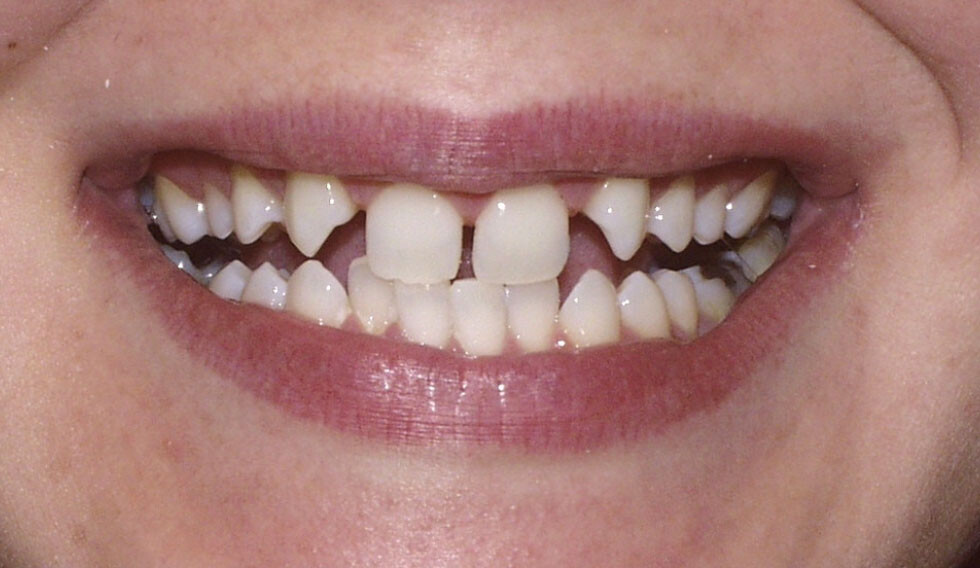

Congenitally missing teeth or hypodontia is a condition where some of the adult teeth do not develop. Although it can also affect the primary teeth, this is quite rare, unless there is an underlying genetic disorder.

Third molars (wisdom teeth) are the most commonly missing but are not included in the definition of hypodontia. This is because it is considered a variation of normal to have missing wisdom teeth. The other most commonly missing teeth are lower second premolars and the upper lateral incisors.

Your dental professional will be able to tell if you have any missing teeth. Usually, they will need an x-ray to confirm this. Gaps between your teeth, losing a baby tooth with no adult tooth taking its place or having a baby tooth longer than normal are all signs of having congenitally missing teeth.